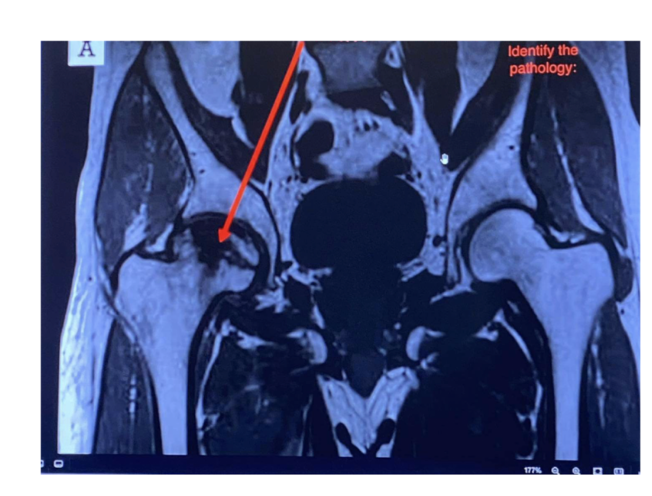

What is the sequence + pathology?

• T1 – fat is bright fluid is dark

• Path = avascular necrosis of the

femoral head

• Lost blood supply to the femoral

head. = bone death

• Decreased signal = oedema